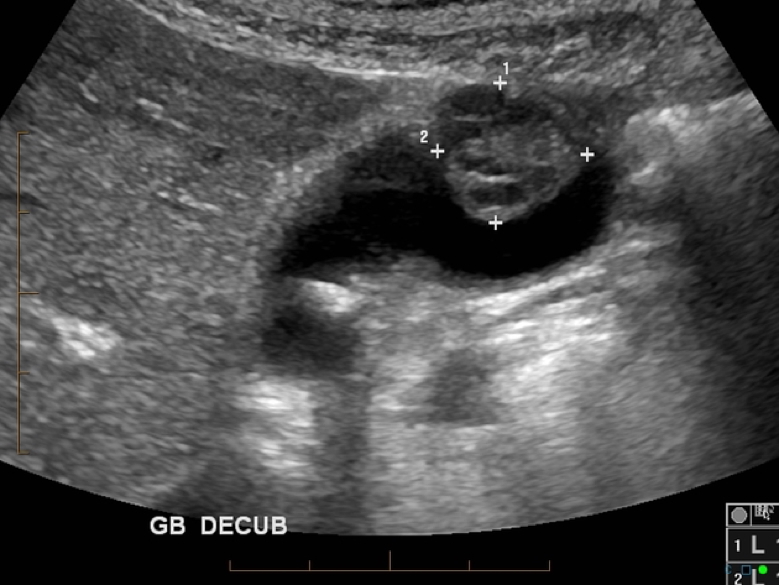

- Imaging:

- CT scan → for diagnosis, staging, and resectability

2. https://radiopaedia.org/cases/gallbladder-carcinoma-10?lang=us